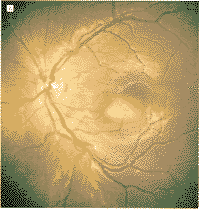

1994年12月18日,随诊检查1例3岁调节性内斜视日本女童时,发现双侧脉络膜病变,除血清肌酸磷酸酶升高外,其病史无特殊。每只眼均可见1个扁平黄色脉络膜病变(图1)。荧光血管造影检查显示两眼病变在早期呈低荧光,晚期呈高荧光(图2)。由于阻塞,吲哚花青绿血管造影检查,早期显示低荧光,晚期发生病变染色(图3)。超声检查(A超和B超)显示双侧明显的脉络膜病变,有高的内反射,符合钙化。计算机断层扫描显示双眼内有钙质沉积(图4)。在T1权重的核磁共振图像显示病变被钆(gadolinium)轻度增强。根据这些发现,诊断为脉络膜骨瘤。约2年后,双眼病变明显增大(图5),由荧光素和吲哚绿血管造影检查所确定。此时,双眼矫正视力仍为20/30,没有弱视的征象。对患者进行随诊,对肿瘤未予治疗。

图1 1994年12月右眼(A)和左眼(B)病变在眼底镜下所见